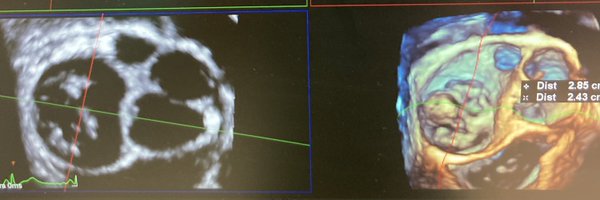

Superior venous sinus interatrial communication @NMerke @fiore_corrado @josecaferca @marciomp50 @alexsfelixecho @RODRIGOVISCONT1 @ASE360 @echo_stepbystep @alex1708ander